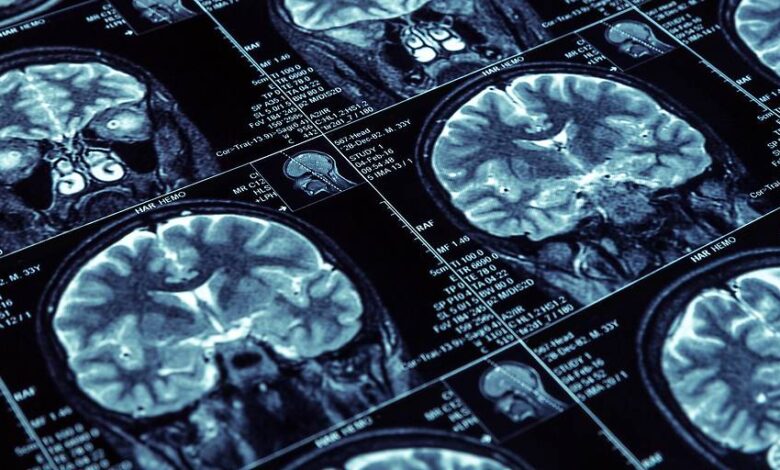

يقال إن Lecanemab فعال ضد مرض الزهايمر وقد تمت الموافقة عليه بالفعل في الولايات المتحدة منذ بداية عام 2023. في أوروبا ، أعلنت وكالة الأدوية الأوروبية الآن أن خطر الآثار الجانبية الخطيرة للجسم المضاد أعلى من التأثير الإيجابي المتوقع. على وجه الخصوص ، أشارت السلطة إلى احتمال احتباس الماء والنزيف في أدمغة الأشخاص الذين عولجوا بالتحضير.

لذلك كان من الممكن تقليل علامات مرض الزهايمر لدى الأشخاص الذين تلقوا الدواء: انخفضت الرواسب الضارة في الدماغ – ولكن على حساب الآثار الجانبية الخطيرة في بعض الأحيان مثل التورم والنزيف في الدماغ. نادرا ما تحدث هذه ، ولكن بعد أن تعتبر EMA أن التأثير الإيجابي للدواء منخفض إلى حد ما ، أدى ذلك إلى رفض النظر ، وفقا للبيان الرسمي للسلطة الأوروبية.